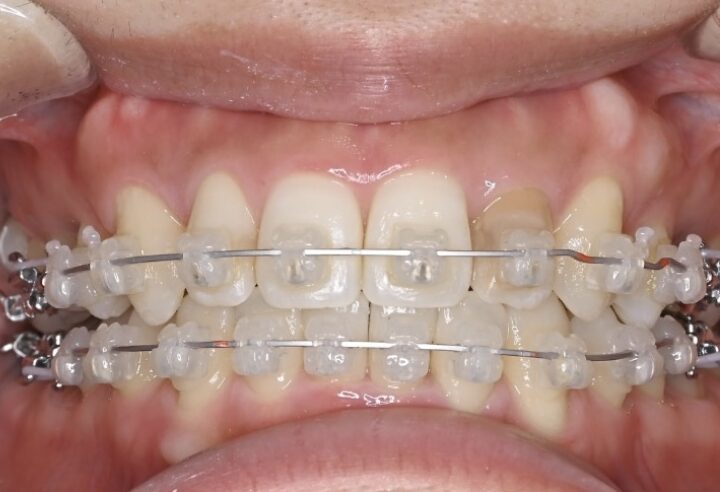

治療経過(1年後)

治療開始からわずか1年で、

✅ 前歯のガタガタがかなり整いました

✅ 前歯の噛み合わせも改善しました

写真で比較すると、その変化は一目瞭然です。

内側を向いていた上の前歯は良い角度になり、下の前歯も正常に近い見え具合となりました。抜いたところの隙間は順調に閉じ、ガタガタもなくなりました。